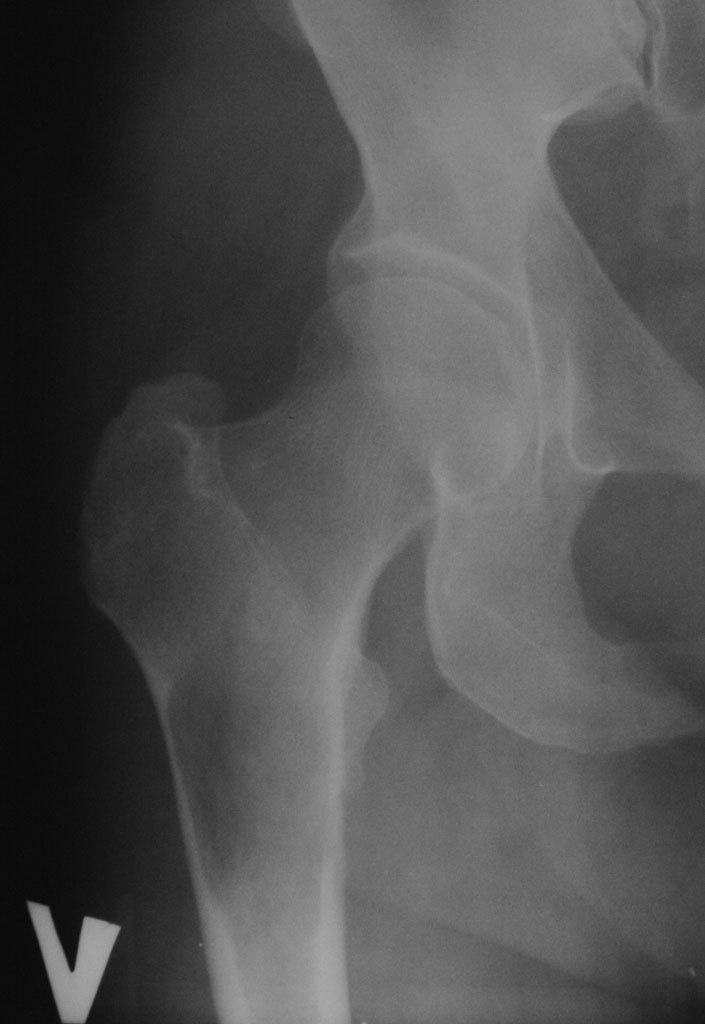

Добрый день. 2,5 месяца назад пациентке по поводу патологического чрезвертельного перелома правой бедренной кости (киста) был выполнена закрытая репозиция и БИОС гамма-гвоздем Stryker с заполнением полости Hydroset.

Гистологическое заключение: участки остеонекроза,хроническое воспаление. На этой неделе больная обратилась с жалобами на боли в области левого тазобедренного сустава. Со стороны оперированной ноги жалоб нет. Проведенное рентгенобследование выявило наличие полостного образования в проксимальном метадиафизе левой бедренной кости, перелом наружной стенки. Планируем выполнить БИОСлевой бедренной кости по методике аналогичной на правой ноге и этому случаю Какой фиксатор выбрать: длинную гамму или универсальный бедренный гвоздь?